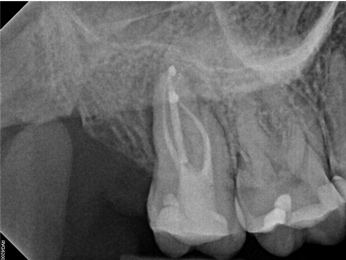

In the first case study, a young female patient was told she had a tooth (tooth No. 2, Figure 3) that should be extracted due to extensive bone loss. Using CBCT, the clinician was able to identify a large lateral canal within the palatal root. Despite the bone loss, the patient was eager to save her tooth. He offered to treat the tooth with the broad-spectrum acoustic technology. As shown in Figure 4, the preparation space was much smaller, which he was able to obturate efficiently. In addition, the small pinpoint of sealer in the middle of the palatal root indicated that the palatal lateral canal had been addressed (Figure 5). In the clinician's opinion, this area was likely the primary source of much of the bone loss.

Fig 3. Case 1: CBCT showed a large lateral canal within the palatal root (Fig 3). There was a small preparation space, which was efficiently obturated (Fig 4). A small pinpoint of sealer in the middle of the palatal root indicated that the palatal lateral canal had been addressed (Fig 5). After 5 months, CBCT demonstrated complete healing (Fig 6), notably on the distal, where probing had resolved to 2 mm. Radiographic images were taken immediately postoperatively (Fig 7) and 5 months postoperatively (Fig 8).

Figure 3

Fig 4. Case 1: CBCT showed a large lateral canal within the palatal root (Fig 3). There was a small preparation space, which was efficiently obturated (Fig 4). A small pinpoint of sealer in the middle of the palatal root indicated that the palatal lateral canal had been addressed (Fig 5). After 5 months, CBCT demonstrated complete healing (Fig 6), notably on the distal, where probing had resolved to 2 mm. Radiographic images were taken immediately postoperatively (Fig 7) and 5 months postoperatively (Fig 8).

Figure 4

Fig 5. Case 1: CBCT showed a large lateral canal within the palatal root (Fig 3). There was a small preparation space, which was efficiently obturated (Fig 4). A small pinpoint of sealer in the middle of the palatal root indicated that the palatal lateral canal had been addressed (Fig 5). After 5 months, CBCT demonstrated complete healing (Fig 6), notably on the distal, where probing had resolved to 2 mm. Radiographic images were taken immediately postoperatively (Fig 7) and 5 months postoperatively (Fig 8).

Figure 5